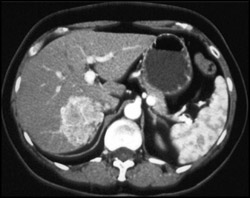

Diagnosis

Hemangioma